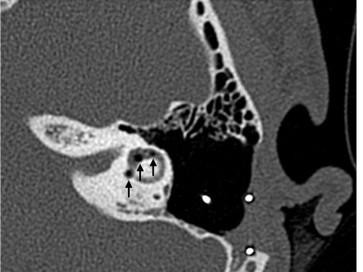

Bei einer Patientin mit beidseitigen Cochlea-Implantaten kommt es nach jeweils zwei Flugreisen zu schwerwiegenden Dysfunktionen des Implantats. Als Ursache für das im CT festgestellte Pneumolabyrinth wird jeweils eine Perilymphfistel vermutet und entfernt. Dies ist jedoch nicht die eigentliche Ursache.

Aufbau bei einer endoskopische Mittelohrchirurgie/© Mir-Salim P., Berlin, In-Ear-Kophörer/© diy13 / Stock.adobe.com (Symbolbild mit Fotomodell), CT des Felsenbeins bei Osteomyelitis der Schädelbasis/© Dewenter I.. et al. doi.org/10.1007/s00106-025-01649-6 unter CC-BY 4.0, Mikrobiom auf der Haut am Finger/© STEVE GSCHMEISSNER/SCIENCE PHOTO LIBRARY /Getty images / iStock, Otitis externa/© Dr. P. Marazzi / Science Photo Library (Symbolbild), Mann hält sich eine Hand ans Ohr/© herlanzer / stock.adobe.com (Symbolbild mit Fotomodell), Älterer Mann legt ein Hörgerät an/© VioletaStoimenova / Getty Images / iStock (Symbolbild mit Fotomodell), Kleinkind mit Cochleaimplantat/© satura86 / Getty Images / iStock (Symbolbild mit Fotomodell), Älterer Mann fasst sich ans Ohr/© Nes / Getty Images / iStock (Symbolbild mit Fotomodell), Ein Arzt bereitet das Hörscreening bei einer Frau vor/© kaisersosa67 / Getty Images / iStock (Symbolbild mit Fotomodell), Otoskopie bei einem jungen Kind/© SolStock / Getty Images / iStock (Symbolbild mit Fotomodellen), Hörgerät im Ohr einer älteren Person /© edwardolive / stock.adobe.com (Symbolbild mit Fotmodell), Frau mit schmerzverzerrtem Gesicht in Wohnzimmer/© fizkes / stock.adobe.com (Symbolbild mit Fotomodell), Mann erleidet Schwindel/© Tunatura / Getty Images / iStock (Symbolbild mit Fotomodell), Frau mit Kopfschmerzen/© MaximFesenko / Getty Images / iStock (Symbolbild mit Fotomodell), Eine ältere Frau riecht an einem Basilikumblatt/© Halfpoint / Stock.adobe.com (Symbolbild mit Fotomodell), Otoskopie in der Praxis/© RomanR / stock.adobe.com (Symbolbild mit Fotomodell), Person hält Medikamente/© fizkes / Stock.adobe.com (Symbolbild mit Fotomodell), Titel/© J. Hornung, Erlangen, Cholesterolgranulom im MRT/© Frederik F/ all rights reserved Springer Medizin Verlag GmbH, Tampanometrie bei einem Kind/© peakSTOCK / Getty Images / iStock (Symbolbild mit Fotomodell), Kleine Saktosalpinx rechts /© Universitätsklinikum Carl Gustav Carus, Dresden, Tympanometrie bei einer Frau/© Viacheslav Yakobchuk (Symbolbild mit Fotomodell), Hörgerät Modell/© Kaulitz S et al. / all rights reserved Springer Medizin Verlag GmbH, Eine Lehrende Person unterhält sich mit einem Kind mit Cochlea-Implantat/© vgajic / Getty Images / iStock (Symbolbild mit Fotomodell), Mann mit Zeichen einer Schwerhörigkeit/© Rido / stock.adobe.com, Computertomographie Felsenbein links /© Marti S et al. doi.org/10.1007/s00106-025-01602-7 unter CC-BY 4.0, Neugeborenen-Hörscreening/© isayildiz / Getty Images / iStock (Symbolbild mit Fotomodell), Eine Frau steckt sich die Finger in die Ohren zum Schutz vor Lärm/© apomares / Getty Images / iStock (Symbolbild mit Fotomodell), Atemwegsinfektionen/© (M) RFBSIP / stock.adobe.com / stock.adobe.com (Symbolbild mit Fotomodellen), Search Icon, HNO-Untersuchung beim Jungen/© adamkaz / Getty Images / iStock (Symbolbild mit Fotomodellen), Infusion/© georgeoprea9 / Getty Images / iStock